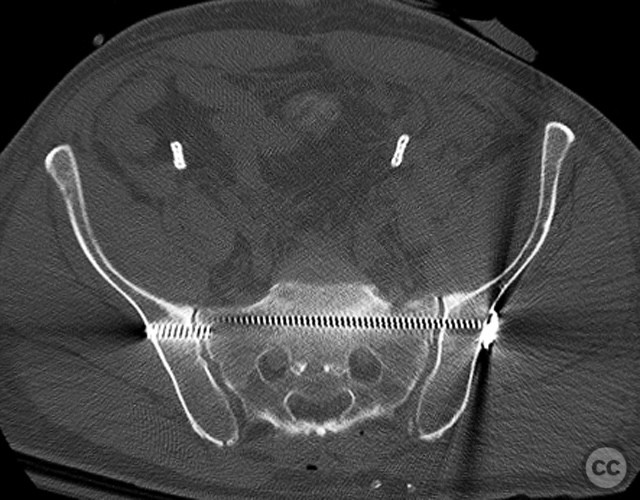

Anatomical surgical approach:  Anteriorly, a low midline infraumbilical incision was made to expose the symphysis pubis, with subperiosteal dissection of the rectus sheath and direct visualization of the disrupted symphysis. Posteriorly, a longitudinal midline approach over the sacrum was utilized, incorporating the traumatic wound for I&D. Deep dissection allowed access to the sacral ala and SI joint. A tenaculum clamp was applied percutaneously to achieve reduction of the sacral/SI fracture-dislocation. Iliosacral screws were inserted percutaneously under fluoroscopic control across the SI joint into S1.

The sequence of anterior then posterior fixation allowed unimpeded access to both injury sites. The use of a tenaculum clamp facilitated reduction of the complex posterior injury. No technical interference was encountered between anterior plate fixation and subsequent posterior iliosacral screw placement. The presence of embolic coils did not impede surgical access or reduction maneuvers.

Orthopaedic implants used:   3.5 mm anterior symphyseal plate, cannulated iliosacral screws